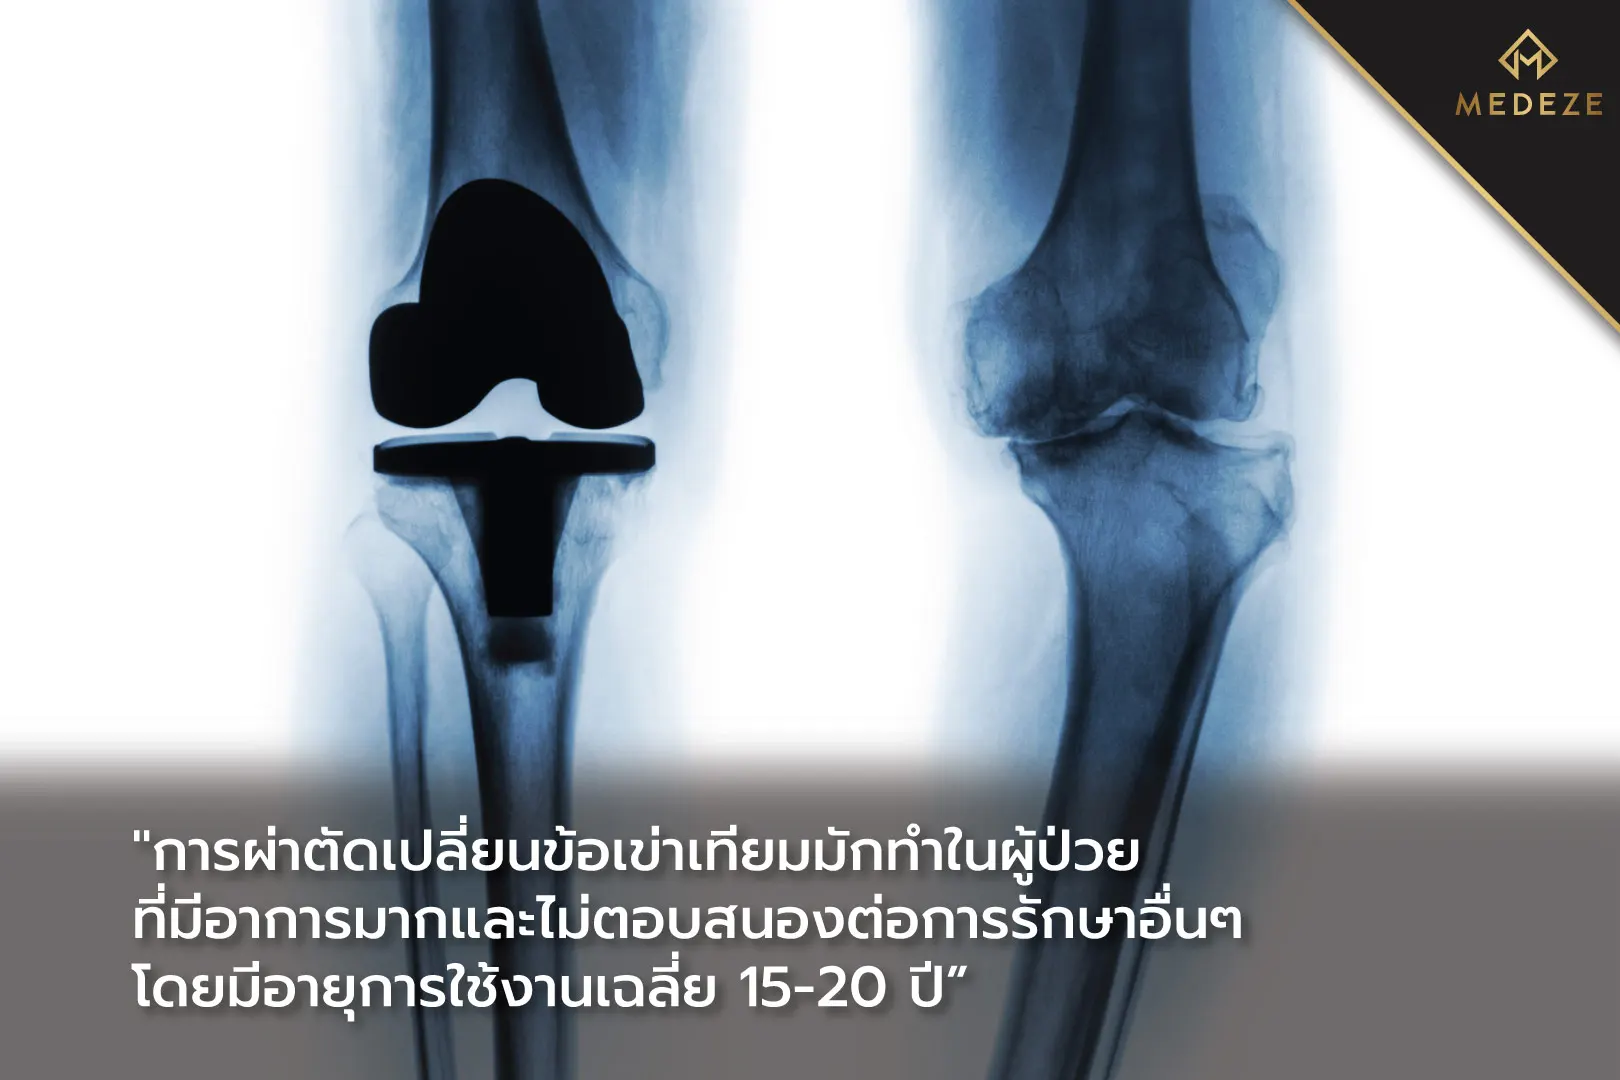

ในการรักษาภาวะข้อเข่าเสื่อมนั้นมักเริ่มจากการปรับเปลี่ยนวิถีชีวิต งดเว้นกิจกรรมที่มีการงอเข่าเช่นการนั่งพับเพียบ ลดน้ำหนัก ทานยาเพื่อบรรเทาอาการปวดหรือยาลดการอักเสบ การรักษาด้วยกายภาพบำบัด การใช้อุปกรณ์พยุงเข่าชั่วคราว การฉีดสารลดการอักเสบหรือสารหล่อลื่นเทียมเข้าไปในข้อเข่า หรือการผ่าตัดเปลี่ยนข้อเข่าเทียมในกรณีที่มีอาการมากและไม่ตอบสนองต่อการรักษาอื่น ๆ [1,2]

- การผ่าตัดเปลี่ยนข้อเข่าเทียมโดยใช้หุ่นยนต์เข้าช่วยการผ่าตัด

การผ่าตัดเปลี่ยนข้อโดยมีหุ่นยนต์ช่วยผ่าตัดนั้นสามารถเพิ่มความแม่นยำในการผ่าตัดและการจัดตำแหน่งของข้อเทียม